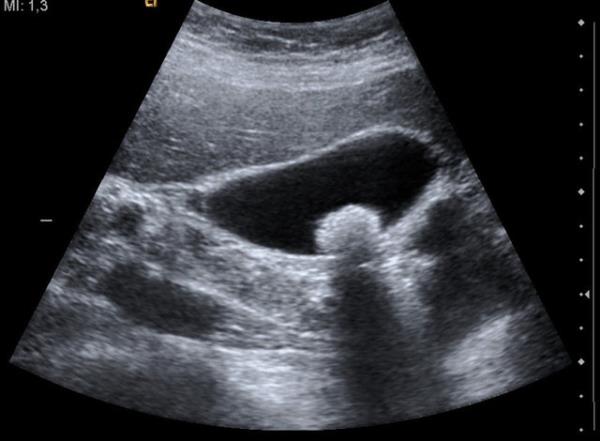

34. Safra kesesi taşı ve iltihabının, detaylı muayene ile (ultrasonografi,kan tetkikleri,MRCP,ERCP,bilgisayarlı tomografi) teşhis ediliyor.

Safra kesesi taşı ve iltihabının, detaylı muayene ile (ultrasonografi,kan tetkikleri,MRCP,ERCP,bilgisayarlı tomografi) teşhis ediliyor.